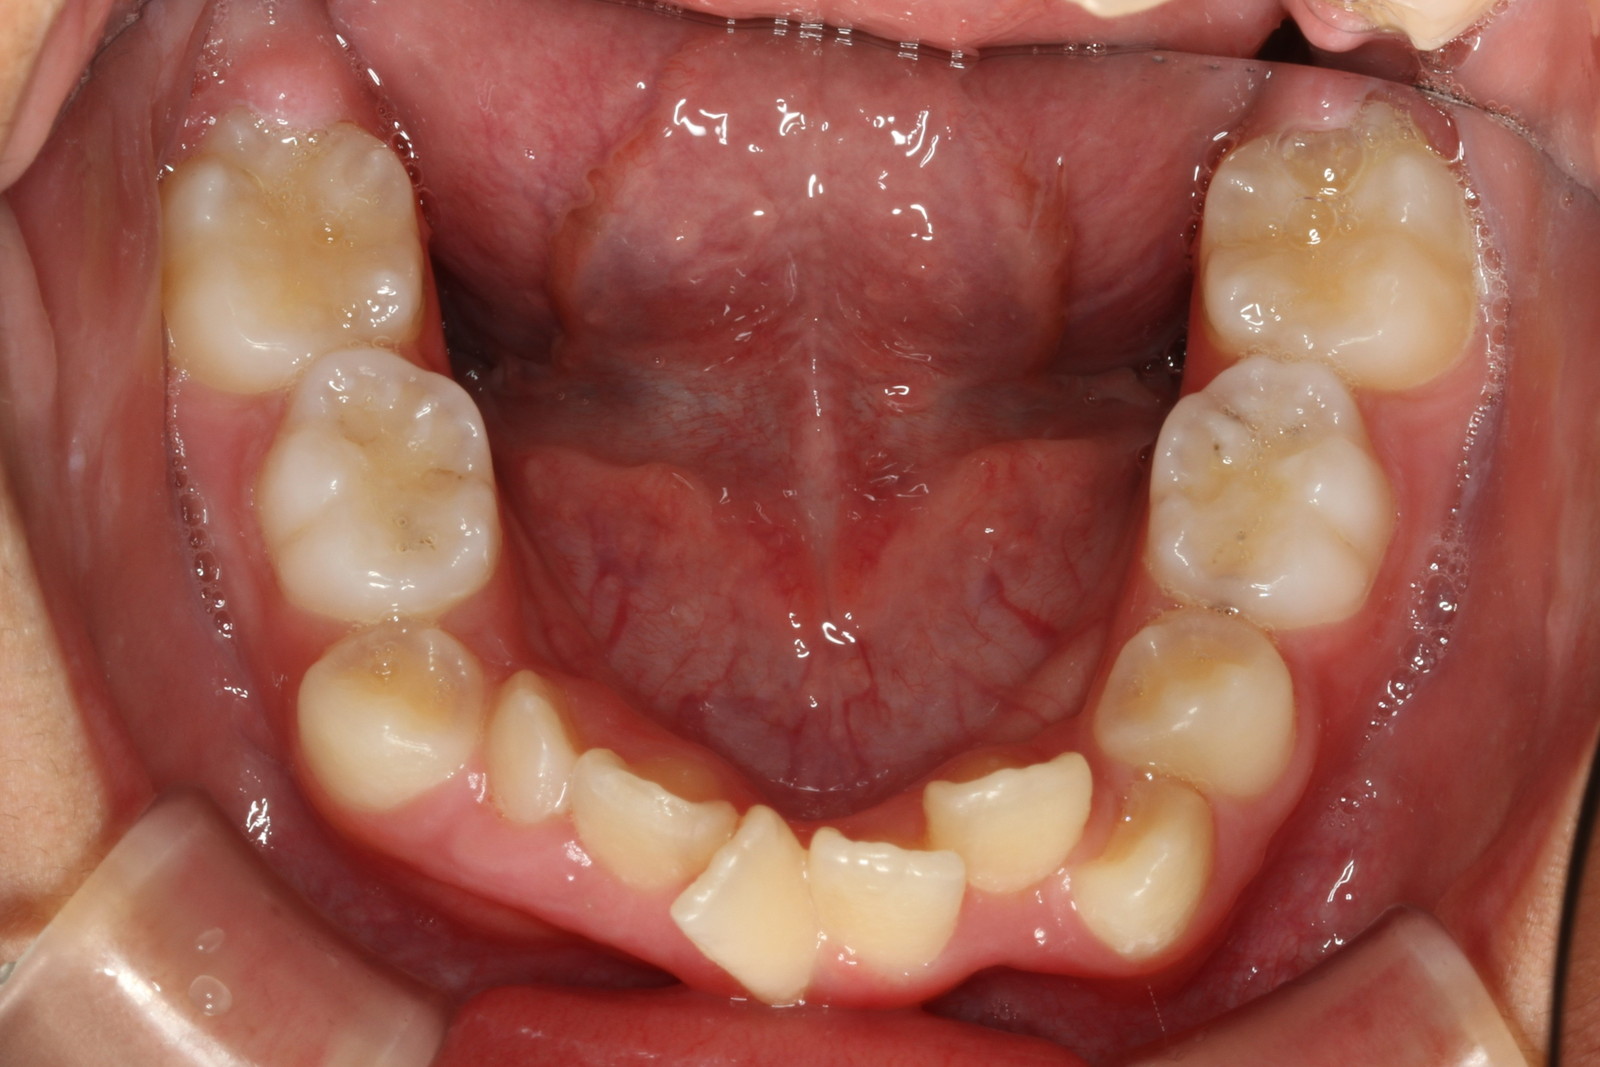

問診を行い、お口の悩みや希望を確認します。レントゲン撮影や口腔内写真の撮影など、必要に応じた精密検査を行います。